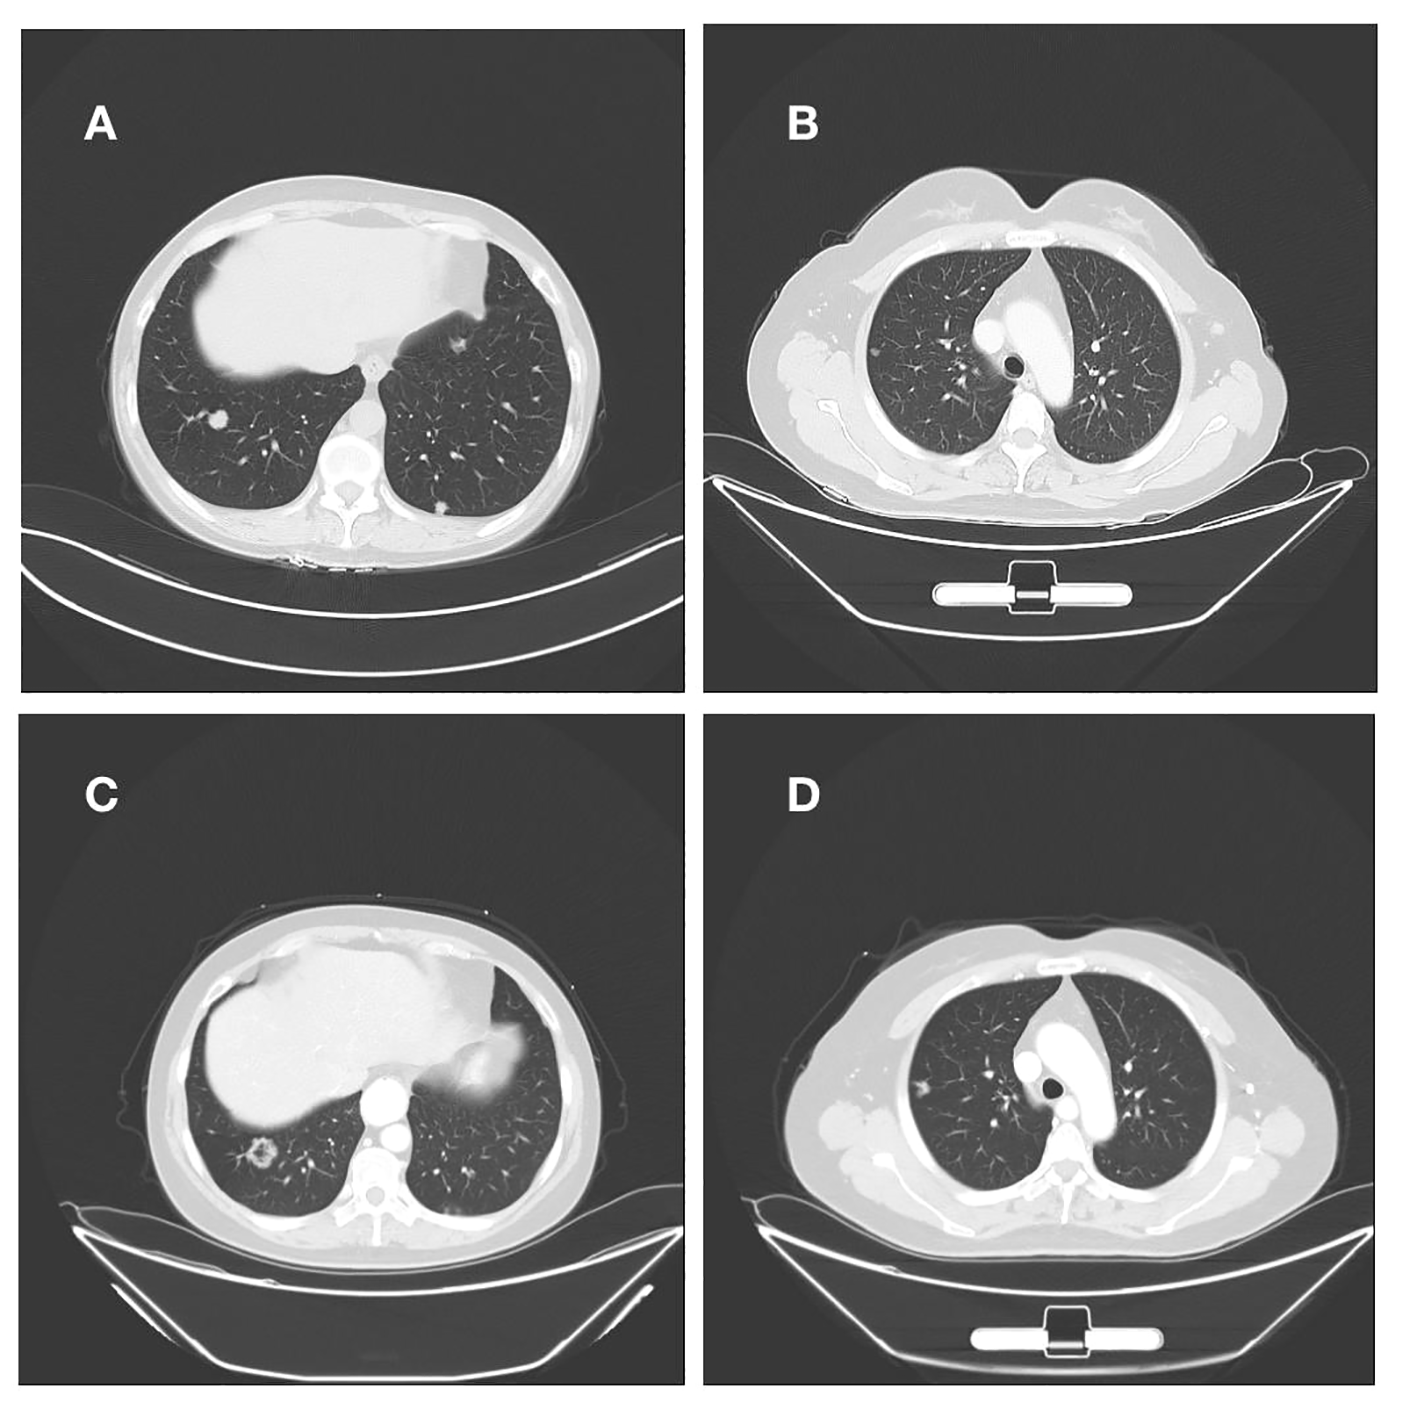

The patient had endometrial mucinous adenocarcinoma, and we used IHC to check for the expression of mismatch repair protein and programmed cell death-ligand 1 (PD-L1). This revealed that MLH1 (+, normal), MSH2 (+, normal), MSH6 (+, normal), PMS2 (+, normal), and the tumor tissue PD-L1 expression: Combination positive score(CPS) was 0, in agreement with the findings of the DNA test. IHC and genetic testing both indicated that the DNA mismatch repair system was effective. Immune checkpoint inhibitors are not an option for the patient’s treatment. After then, we modified the therapy to include albumin-bound paclitaxel, carboplatin, and bevacizumab. After four cycles of the aforementioned regimen, repeated CT scans revealed a right lung lesion that had advanced and was about 1.7 cm in diameter. Following two cycles of treatment, the efficacy was assessed for progressive disease (PD) and endometrial cancer recurrence, drawing on the treatment of mucinous adenocarcinoma of the ovary. This patient received oxaliplatin 150 mg intravenous chemotherapy combined with anlotinib capsules 10 mg orally, and after two cycles of treatment evaluated with multiple met During three chemotherapy rounds, a second CT scan revealed that both lung tumors had continued to advance and that numerous additional peritoneal and omental metastases had also developed(Figure 3). During therapy and the unchecked course of the illness, the patient never contracted Covid-19/Omicron.

Figure 3

(A, B) Right lung nodule on initial admission; (C, D) Persistent progression of right lung metastases after multiple cycles of treatment.